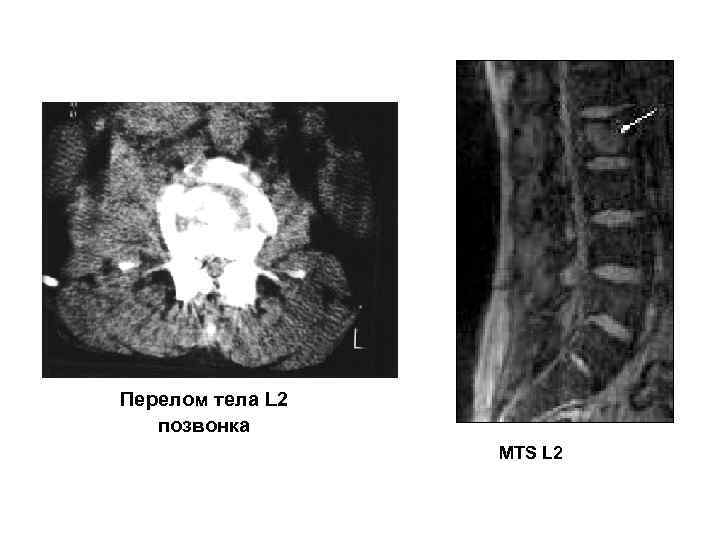

Перелом тела L 2 позвонка MTS L 2